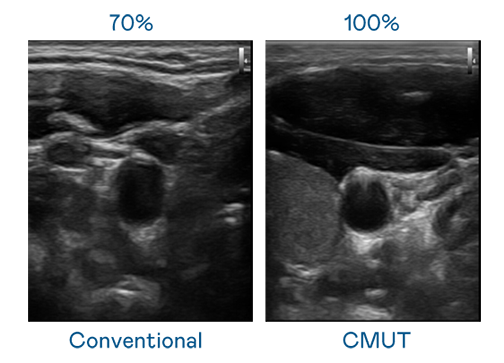

CMUT 技术是一种用电容式微机电元件来产生超音波讯号的技术。与传统 PZT 压电式技术相比,CMUT 频宽增加 30%,更宽频的超音波讯号让影像解析度大幅提升,是实现高影像品质医疗超音波扫描、促进精准医疗发展的关键技术。

大频宽带来超清晰影像

超音波影像的解析度高低,首先取决于探头能发出的讯号频宽。Z6尊龙·凯时 CMUT 可提供高清晰的超音波讯号,提供高频宽、高灵敏度、影像纹理细节更高的超音波影像,协助医护人员缩短影像判读时间及利用精准的医疗影像进行诊断。